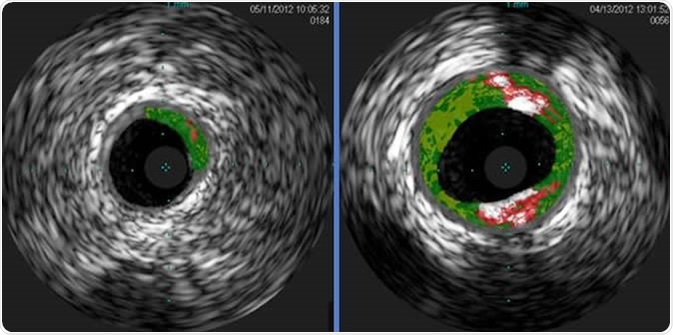

Shown are cross-sectional ultrasound images of coronary arteries from patients enrolled in a study. Plaque buildup (colored areas) in an artery from a patient that lacks sensitivity to red meat allergen (left) is much lower than plaque levels in an artery from a patient with sensitivity to red meat allergen (right). Courtesy of Angela Taylor, M.D., University of Virginia Health System